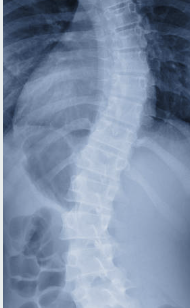

허리 협착증이 의심되면 병원에서 정밀 검사를 통해 진단을 받아야 해요. 주요 진단 방법은 다음과 같습니다.

- X-ray 검사: 척추의 구조 변화를 확인할 수 있어요.